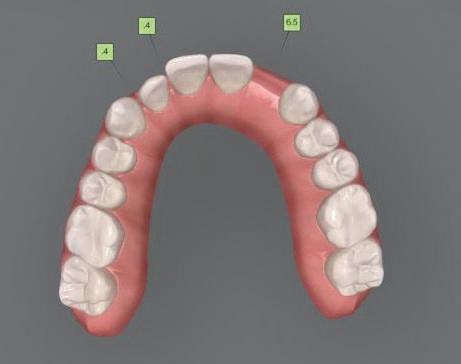

та челюст 4 минивинта (TADs) бяха по ставени в максилата – 2 в небцето и 2 интрарадикуларно във фронта, с цел да се извърши интрузия на цялата зъбна дъга, да се коригира гингивалната усмивка и да се позволи провеждането на обратна на часовниковата стрелка авторо

орални снимки и снимки на позата, пал пация на мускулите, брукс-чекър, оклу зограми, кондилография, рентгеногра фии, СВСТ и ядрено-магнитен резонанс на темпоромандибуларните стави). Преди началото на ортодонтското лечение всички стари възстановява ния бяха свалени и бяха заменени с дъл госрочни временни от хибридна керами ка. На девитализираните зъби бе прове дено ендодонтско релечение. Индивиду ализиран оклузален сплинт бе направен с цел да се постигне контролирано репо зициониране на долната челюст, като носенето му продължи три месеца до възстановяване на правилната позиция на ставния диск и затихване на орофаци алната болка и дискомфорт в ставата. Брекетите в горната челюст бяха за лепени, за да започне подреждането и нивелирането на зъбите, докато паци ентът все още носеше сплинта. След края на терапията със сплинта бе на правена кондилография, за да се потвър ди триизмерната позиция на долната челюст. След залепване на брекетите в долна

тация на долната челюст. Дъга GUMMETAL с tip-back извивки бе поставена в долната челюст за ниве лиране кривата на Шпее. Случаят бе финализиран с 19x25 SS дъги в горната и долната зъбна дъга за координиране. Преди да се изготви финалният восъ чен моделаж, естетичните и лицеви те характеристики бяха анализирани с помощта на дигитален дизайн на ус мивката, за да се създаде мок-ъп, чии то форма и размери да бъдат одобрени от пациента. Бе оценена фонетиката и бяха заснети лицеви снимки и видеа. Зъ бите бяха изпилени, като препарация та бе изцяло водена от функционалния восъчен моделаж, прехвърлен в устата на пациента. След препарацията восъч ният моделаж бе напаснат и насложен върху препарационния модел и бе фрезо ван от e-max multi bl 1. Циментирането на финалните конструкции бе направе но при изолация с кофердам, следвайки адхезивния протокол. След циментирането бе направено проследяване на оклузията чрез снема не на отпечатъци, монтиране на моде лите в артикулатор в окончателната интеркуспидация и внимателно прове ряване за наличие на блокажи при воде ни движения.